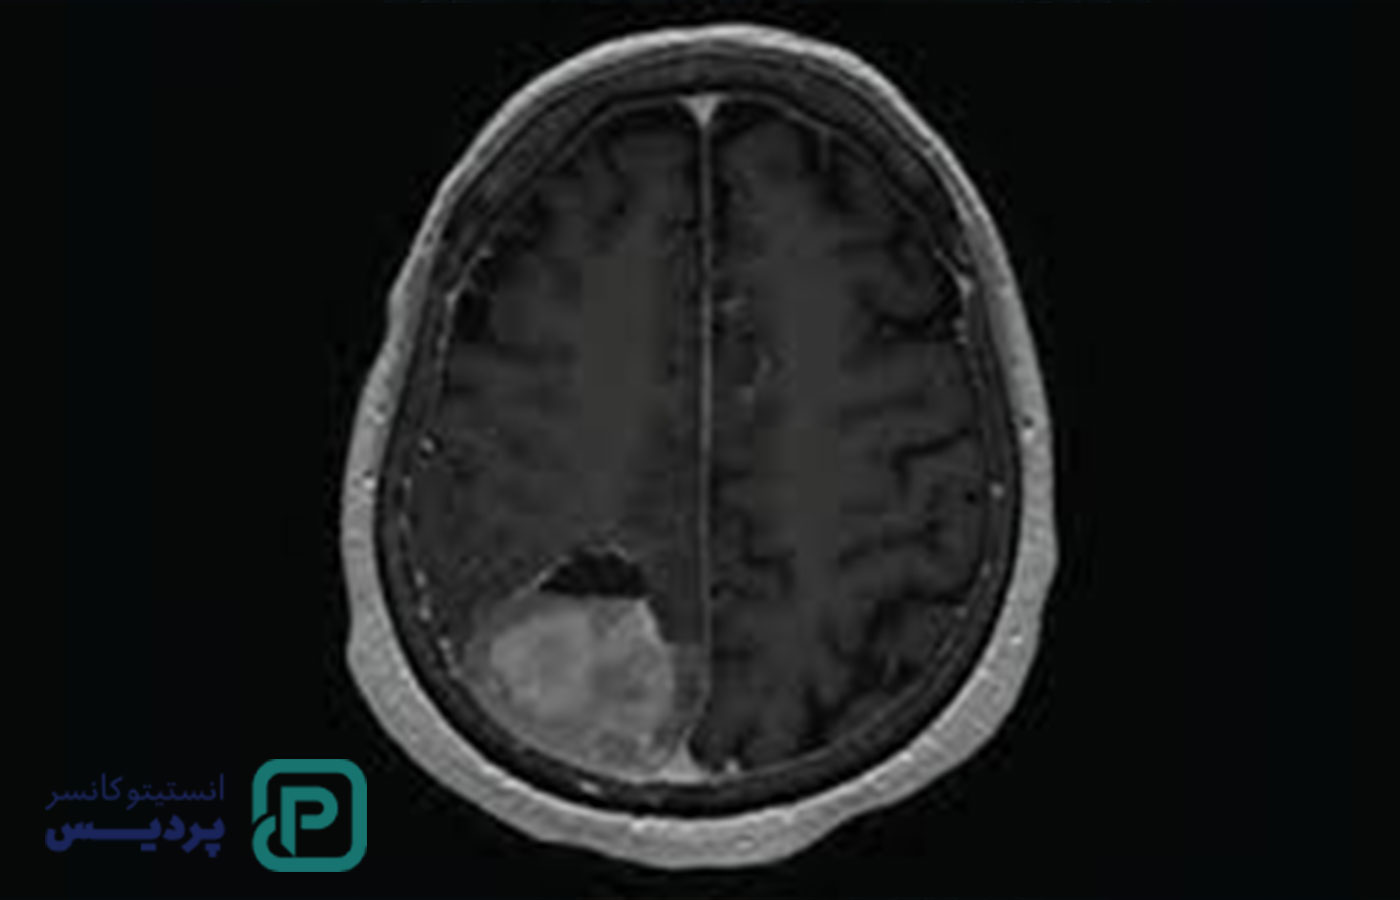

تشخیص تومور مغزی معمولاً با ترکیبی از معاینه بالینی و آزمایشهای تصویربرداری انجام میشود:

MRI و سیتیاسکن: دقیقترین روشها برای مشاهده تومور، محل و اندازه آن هستند.( طبق دادههای موسسه ملی سرطان آمریکا (National Cancer Institute)، تشخیص زودهنگام با MRI و بیوپسی شانس درمان موفق تومورهای مغزی را بهطور چشمگیری افزایش میدهد)